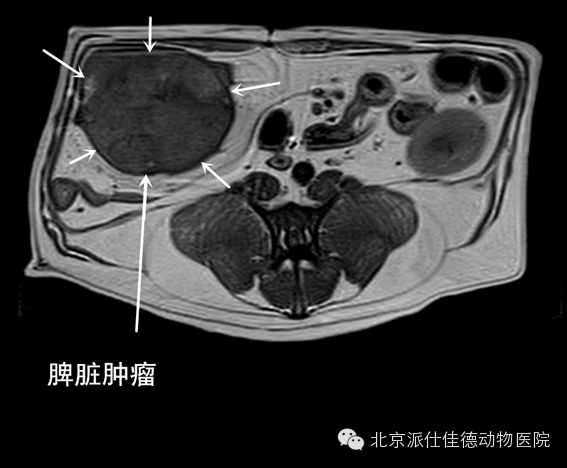

14.有些动物突然出现贫血,也没有发生外伤,腹围突然增大,经检查发现内脏大出血,最常见的是血管瘤破裂,如脾脏肿瘤破溃、肝脏肿瘤破溃、主动脉夹层瘤破裂等等。